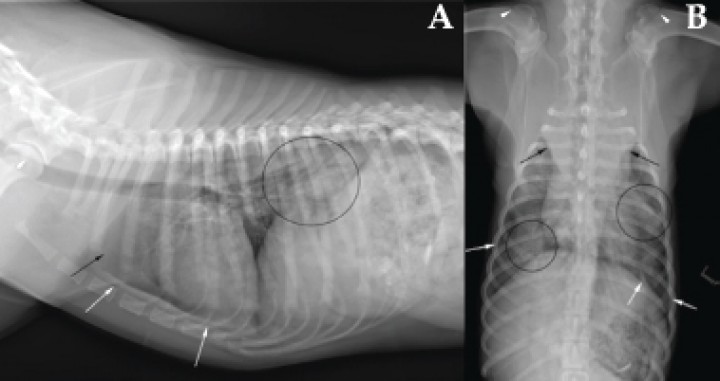

Se presenta un perro joven, macho entero, American Pitbull de 20 kg de peso. Acude a urgencias por sospecha de atropello, ya que fue encontrado junto a una carretera incapaz de mantenerse en estación. En la exploración física se observa taquipnea, disminución de los sonidos respiratorios a la auscultación, dolor a la manipulación del hombro izquierdo y lesiones cutáneas superficiales traumáticas. Las alteraciones analíticas encontradas son anemia leve (hematocrito 36,7 %; valor de referencia: 37,3-61,7 %), leucocitosis (24,63 K/µl; valor de referencia: 5,05-16,76 K/µl), neutrofilia (20,5 K/µl; valor de referencia: 2,95-11,64 K/µl) e incremento de la ALT (206 U/l; valor de referencia: 10-125 U/l). Se realizan radiografías de la cavidad torácica (Fig. 1).

<p>Radiografías del tórax. (<strong>A</strong>) Proyección laterolateral derecha. (<strong>B</strong>) Proyección ventrodorsal.</p>

Radiografías del tórax. (A) Proyección laterolateral derecha. (B) Proyección ventrodorsal.

Se aprecia un patrón intersticial de forma generalizada con áreas focales de patrón alveolar con presencia de broncogramas aéreos de forma bilateral y asimétrica. El mediastino craneal está marcadamente ensanchado por una opacidad tejido blando que provoca desplazamiento de los lóbulos pulmonares craneales hacia lateral y caudal. El repliegue mediastínico caudal está ligeramente ensanchado y se visualiza leve retracción del campo pulmonar respecto de la pared costal en ambos hemitórax. A nivel de estómago se observan múltiples opacidades óseas intraluminales entremezcladas con patrón alimentario normal, sin distensión patológica del mismo. Se observa fisis de crecimiento de la cabeza humeral. No se aprecian lesiones óseas ni de tejidos blandos en las estructuras extratorácicas (Fig. 2).

<p>Radiografías de la Figura 1. Se observan lesiones focales de patrón alveolar con broncogramas aéreos (círculos negros), ensanchamiento del mediastino craneal por opacidad tejido blando (flechas negras) que desplaza los lóbulos pulmonares craneales, ligero ensanchamiento del repliegue mediastínico caudal y leve retracción pulmonar (flechas blancas). Se aprecia la fisis del húmero proximal todavía abierta (puntas de flecha blancas).</p>

Radiografías de la Figura 1. Se observan lesiones focales de patrón alveolar con broncogramas aéreos (círculos negros), ensanchamiento del mediastino craneal por opacidad tejido blando (flechas negras) que desplaza los lóbulos pulmonares craneales, ligero ensanchamiento del repliegue mediastínico caudal y leve retracción pulmonar (flechas blancas). Se aprecia la fisis del húmero proximal todavía abierta (puntas de flecha blancas).